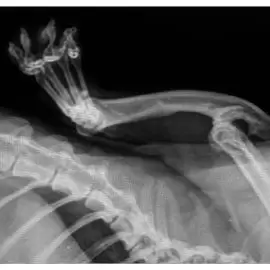

Pierwotna dyskineza rzęsek nie jest choroba tak łatwą do rozpoznania. Wynika to przede wszystkim z rzadkości jej występowania. Drugą sprawą jest to, że wiele przypadków zapewne do tej pory nie zostało zdiagnozowanych. Choroba spowodowana jest przez mutacje w genach kodujących białka odpowiedzialne za tworzenie struktur nabłonkowych zwanych rzęskami. W prawidłowych warunkach rzęski to mikroskopijne włoski wewnątrz dróg oddechowych. Ich celem jest przemieszczanie śluzu w kierunku gardła. Ma to wspomagać jego oczyszczanie.

Na rzęskach zatrzymują się też zanieczyszczenia wciągane z powietrzem do płuc, w tym również bakterie. Rzęski w pewnym stopniu uniemożliwiają bakteriom wniknięcie głęboko do dróg oddechowych. Ich dyskineza to inaczej mała ruchliwość tych rzęsek oraz wici. Choroba objawia się już u noworodka, który ma problem z odkrztuszeniem płynu owodniowego. Chwilę po urodzeniu dziecko ma problemy z oddychaniem, krztusi się, wymiotuje, szybciej oddycha. Często wtedy lekarze decydują się na wsparcie tlenowe dziecka.